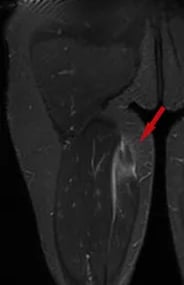

As lesões nos músculos e tendões na coxa geralmente ocorrem após um trauma ou movimento abrupto, relacionado a atividades esportivas. A Ressonância Magnética confirma o diagnóstico.

Lesão do quadríceps: ocorre frequentemente no momento de um chute, acometendo geralmente o reto femoral. Lesões tendíneas costumam causar dor no quadril, enquanto lesões na fibra muscular causam mais dor na coxa. Seu tratamento é com repouso e Fisioterapia na grande maioria dos casos.

Lesão dos isquiotibiais: são os músculos da parte de trás da coxa (semitendíneo, semimembranoso e bíceps femoral); a lesão geralmente ocorre ao se esticar o quadril com o joelho estendido, fazendo com que o paciente sinta dor na parte baixa da nádega ou na coxa, dependendo do local da lesão. Tratam-se as lesões das fibras musculares com repouso e Fisioterapia. Já avulsões tendíneas, podem necessitar de cirurgia, caso haja avulsão de 2 tendões ou mais, com retração maior de 2 centímetros.